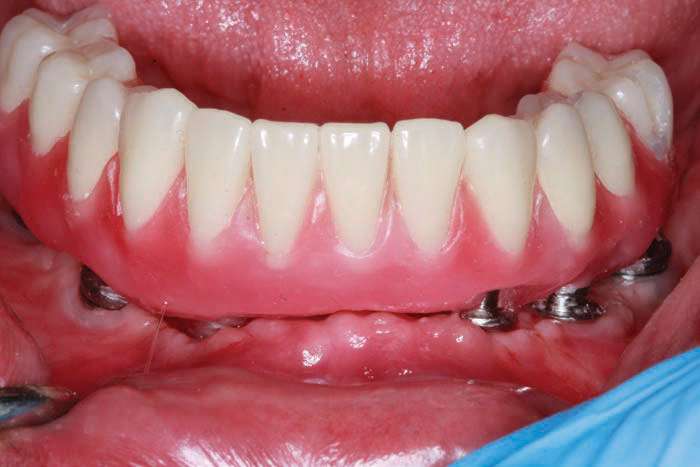

The BioHorizons implants were placed with a good A-P spread, and the bone in the anterior mandible was left in case it was needed at the uncovery appointment (Figure 8). At the uncovery visit, the LightScalpel laser was used to perform a trephine of the posterior implants by placing the surgical guide, marking the osteotomy sites with a Dr. Thompson’s marking stick, and (using a super-pulsed 2W setting) to gently remove the cuff of tissue over the implants (Figure 9). In the anterior mandible, a full-thickness flap was done, and the remaining bone was removed with the PIEZOSURGERY device (Figure 10). The peri-mucosal healing abutments were placed, and a soft-tissue conditioner was placed in the lower denture (Figure 11). After one month of healing, the patient was ready for impressions (Figure 12).

The 3-in-1 abutments are included with the Tapered Internal Dental Implants (BioHorizons) and, when a ball-top screw is placed, these become impression copings (Figure 13a). The initial ball-top screw impression was taken (Aquasil Ultra Xtra Plus [Dentsply Sirona Restorative]) (Figure 13b). This impression material has excellent wettability and tear strength for capturing the subgingival abutment implant interface. The setting time of 5.5 minutes gives adequate working time and is appropriate for larger cases for which an extended working time is desirable.